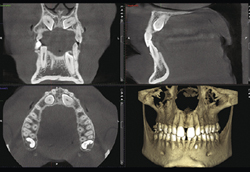

歯科用CT

当院では、3D(3次元)の立体画像からの情報をもとに、今まで見えなかった部分が見えることで、より正確なレントゲン診断ができるようになりました。

さらに、超高解像画像から広範囲撮影まで可能で、医科用CTの約5倍の情報量を得られますので、患者さんにとってより安心で納得の治療がおこなえるようになりました。